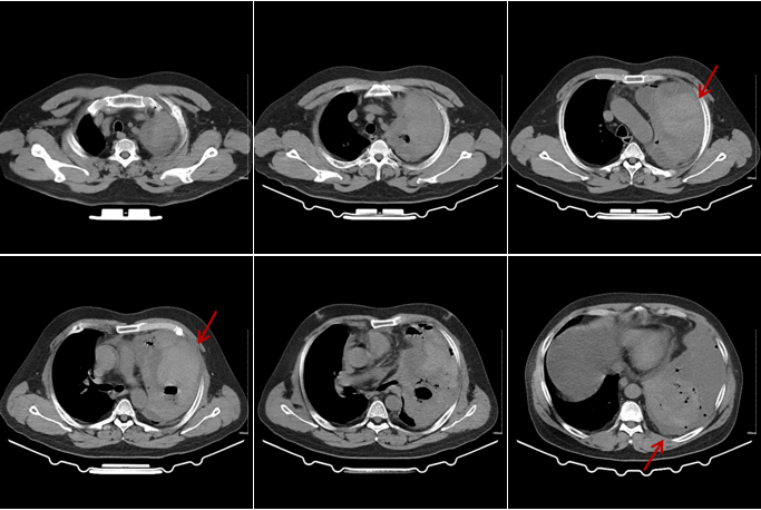

5月5日复查胸部CT:肺渗出病灶较前吸收,右上肺厚壁空洞,左侧胸腔血气胸伴左肺膨胀不全(图7)。支气管动脉CTA示:支气管动脉未见明显异常,未见肺占位;左肺下叶簇状瘤样改变,内见造影剂充盈,边缘光滑清晰,考虑血管改变,三维重建与左肺下叶动脉相连(图8),符合肺动脉瘤诊断。

图片

7  患者胸部CT(2025-05-05)

8  患者支气管动脉CTA(2025-05-05)